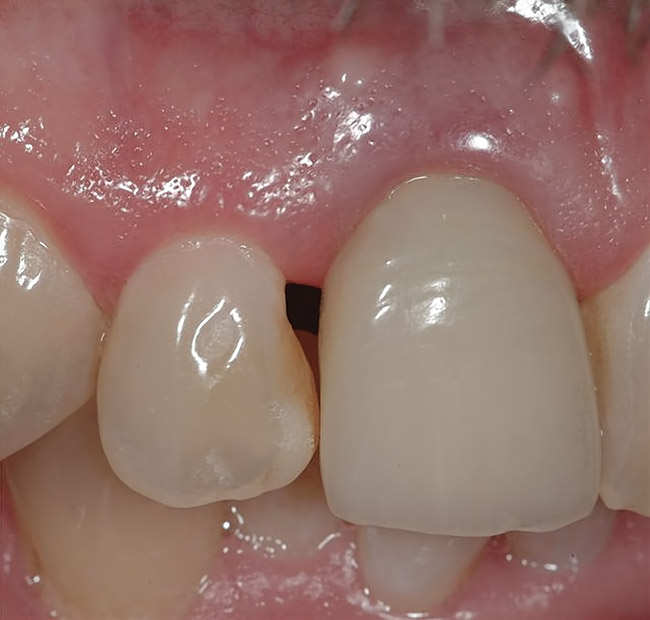

Figure 25  Gingival zenith planning: The location of the gingival zenith for this missing lateral incisor is not fully evident during initial clinical evaluation (Fig 21). Subsequent diagnostic waxing reveals the position of the planned gingival zenith (Fig 22). A thermoplastic template captures the position of the zenith and enables transferring this location to the clinical environment (Fig 23 and Fig 24). Final crown contours are defined by soft-tissue form (Fig 25).

Figure 25

Implant placement according to the 3/2 rule involves using a surgical guide that reveals the location of the gingival zenith. Gingival zenith-oriented planning begins with a diagnostic waxing that identifies the planned tooth contour and related soft-tissue form. This information is transferred to the radiographic assessment and surgical placement using a thermoplastic index that is carefully trimmed to the zenith. In this way, the surgical placement can be monitored and directed from the location of the gingival zenith (Figure 21 through Figure 25). The intended result is placement of the implant/abutment margin 3-mm apical and 2-mm palatal to the clinical landmark. Careful fabrication of the provisional crown guides tissue formation and results in properly developed soft-tissue form surrounding the final implant crown (Figure 25).